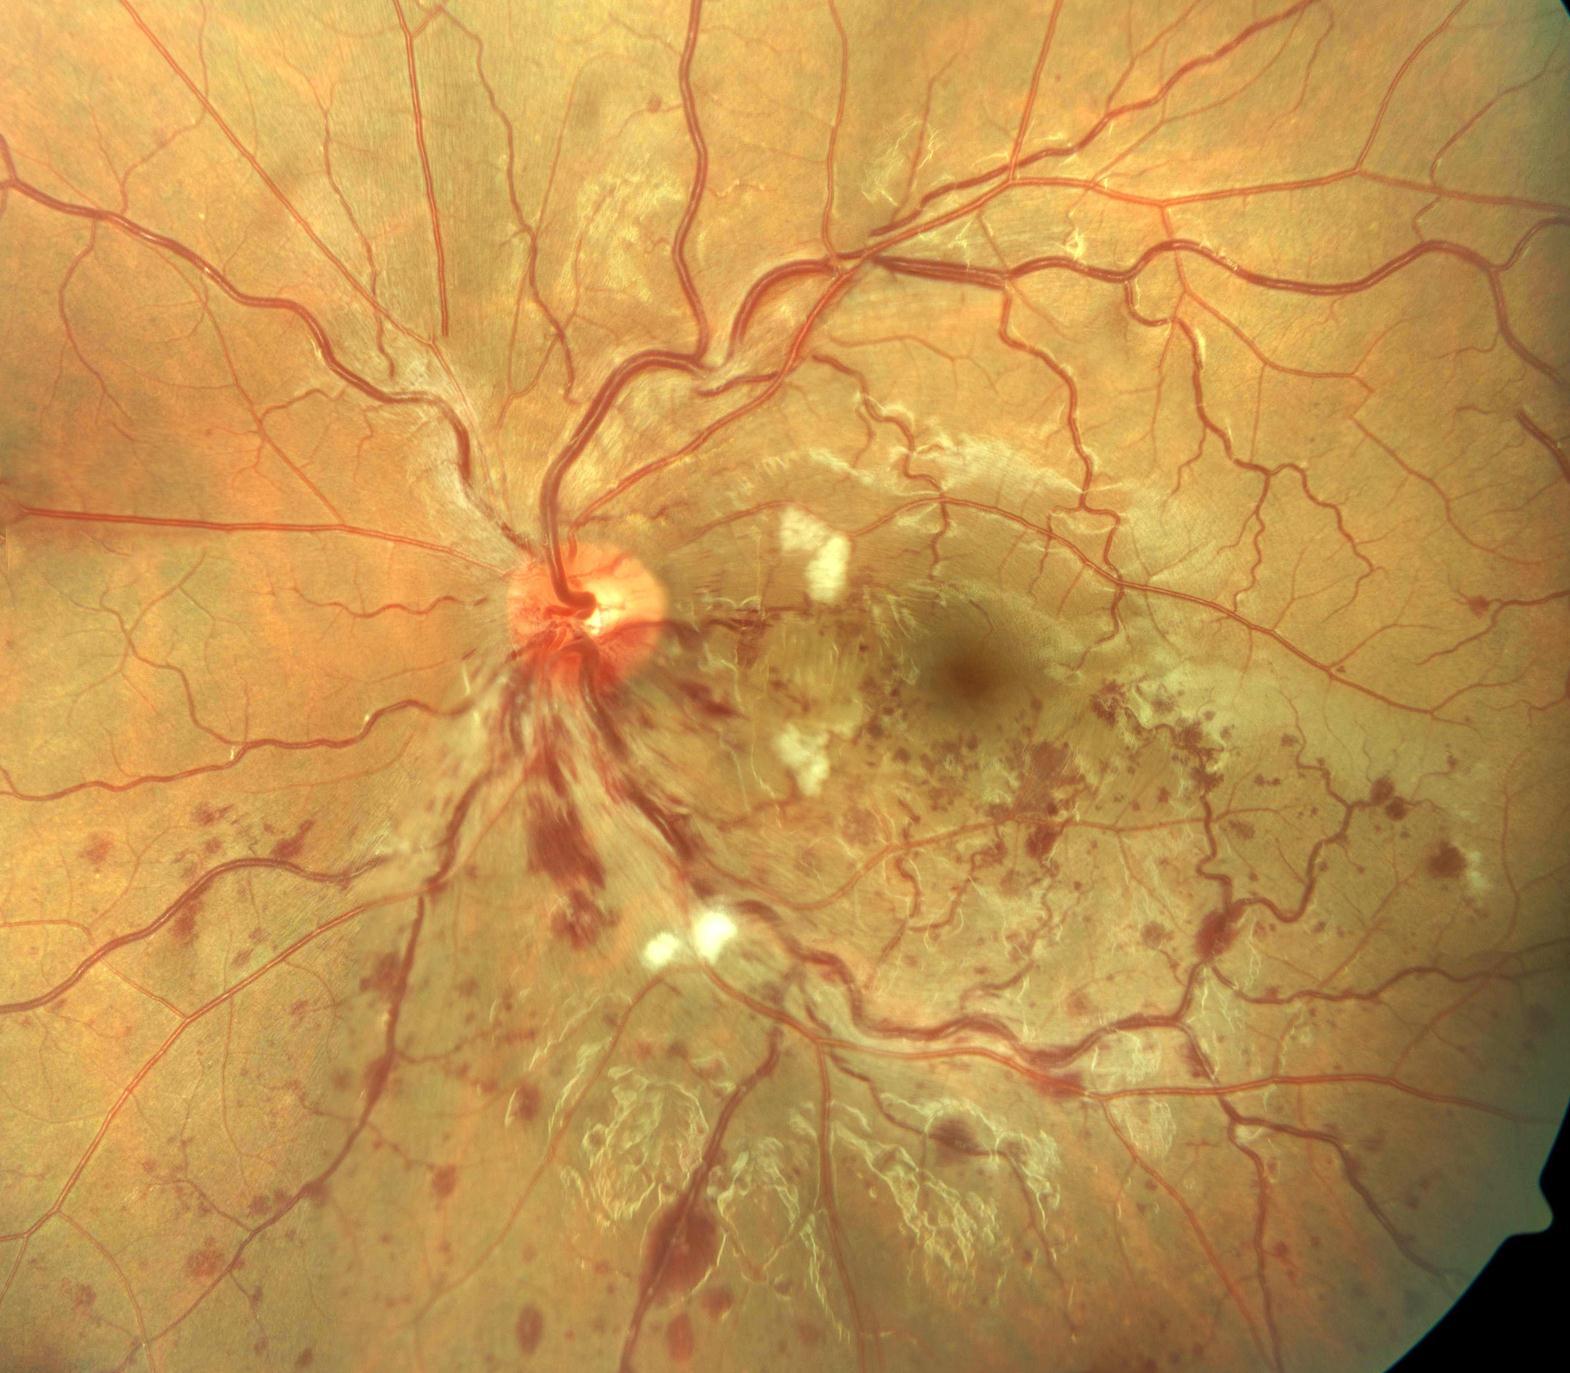

On examination, distant Snellen visual acuity was 6/6 unaided bilaterally. Eyelids, conjunctiva, cornea, anterior chamber, pupils, lens and extraocular range of motion were normal. Assessment of the posterior segment showed inferior BRVO of the left eye (Figure 1). Figure 1 shows dilatation and tortuosity of the affected venous segment, with flame-shaped and dot/blot haemorrhages, retinal edema and cotton wool spots in the section of the retina drained by the obstructed vein. Humphrey visual field testing showed no abnormalities. Fundus flourescein angiography showed features suggestive of left branch retinal vein occlusion (BRVO) with delay in the venous phase. There was no significant capillary fallout.

Figure 1.The figure shows evidence of BRVO in the left eye. There is dilatation and tortuosity of the affected venous segment, with flame-shaped and dot/blot haemorrhages, retinal edema and cotton wool spots in the section of the retina drained by the obstructed vein.